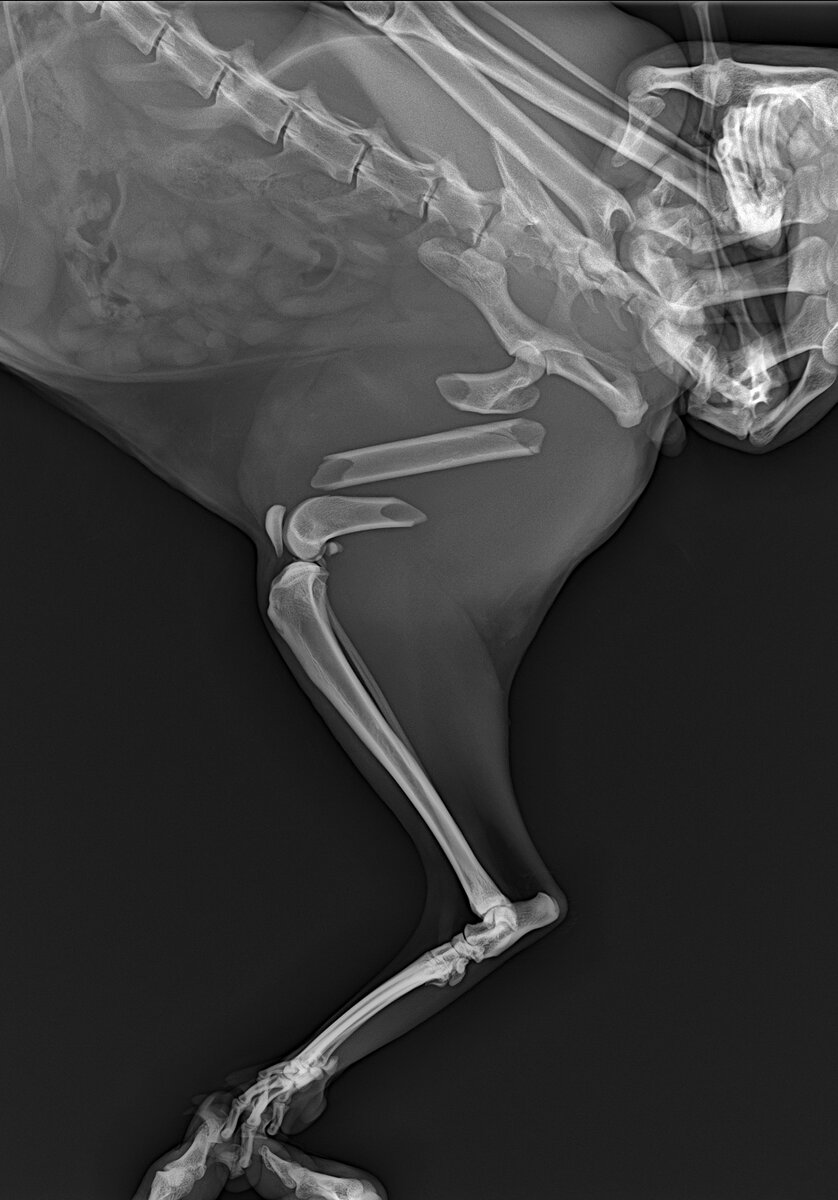

Хищник сломал лапу Остеосинтез бедренной кости правой тазовой конечности. Открытая репозиция отломков, фиксация спицами Киршнера (интромедулярно), серкляжной проволкой, дистальные отломки зафиксированы пластиной с пятью шурупами. Поправляйся усатый!

Остеосинтез бедренной кости правой тазовой конечности. Открытая репозиция отломков, фиксация спицами Киршнера (интромедулярно), серкляжной проволкой, дистальные отломки зафиксированы пластиной с пятью шурупами.